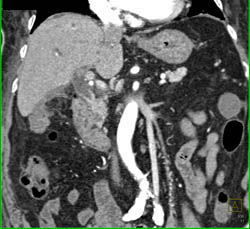

Cholangiocarcinoma of the Distal Common Bile Duct (CBD) Which Is Enhancing- See Full Sequence